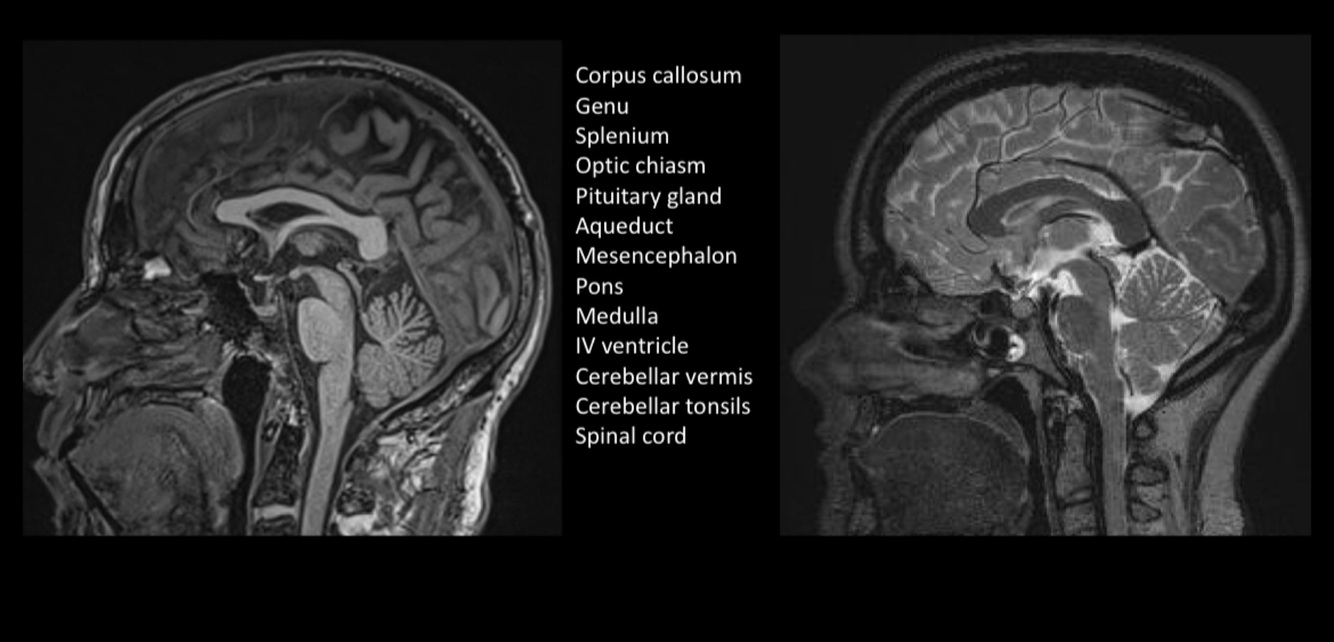

¿Qué técnica observamos?

RESONANCIA MAGNÉTICA